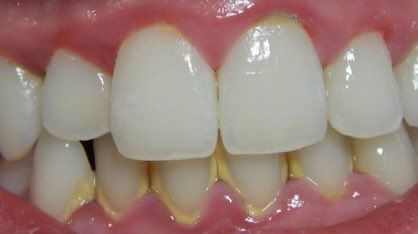

اللثة السليمة:

لمعرفة اللثة المريضة يجب أولا معرفة السليمة ونعرف الاختلافات البسيطة بين جميع الأعراق.اللثة السليمة لونها زهري (غالبا)ملتصقة بالأسنان لامعة(غالبا)لا تنزف عند اللمس أوالتفريش أو بدون سبب/بعض البشرلديهم تصبغات سمراء طبيعية #صحة_أسنانك